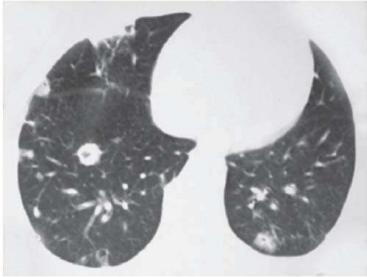

Um paciente de 58 anos de idade, com antecedente pessoal de hipertensão arterial sistêmica, diabetes melito e doença renal crônica estádio 4, pouco aderente ao tratamento medicamentoso, necessitou de internação recente devido a estado hiperglicêmico e hiperosmolar há três semanas. Nesta internação, permaneceu sob cuidados intensivos e, entre outras terapias, foi submetido a quatro sessões de hemodiálise. Desde a alta, melhorou sua adesão medicamentosa, no entanto, vem apresentando calafrios, sudorese e alguns episódios de febre, que o paciente tem atribuído aos medicamentos que agora passou a usar. Há um dia, iniciou quadro de tosse e dor ventilatório-dependente e, devido a isso, resolveu procurar o pronto-socorro. Na triagem, apresentava FC de 101, PA de 160 x 100, T 37,6 e sat. de O2 de 92%. O médico plantonista, sem examinar o doente, solicitou uma tomografia de tórax, que revelou a imagem seguinte.

Com base nesse caso hipotético, assinale a alternativa que apresenta a melhor conduta.